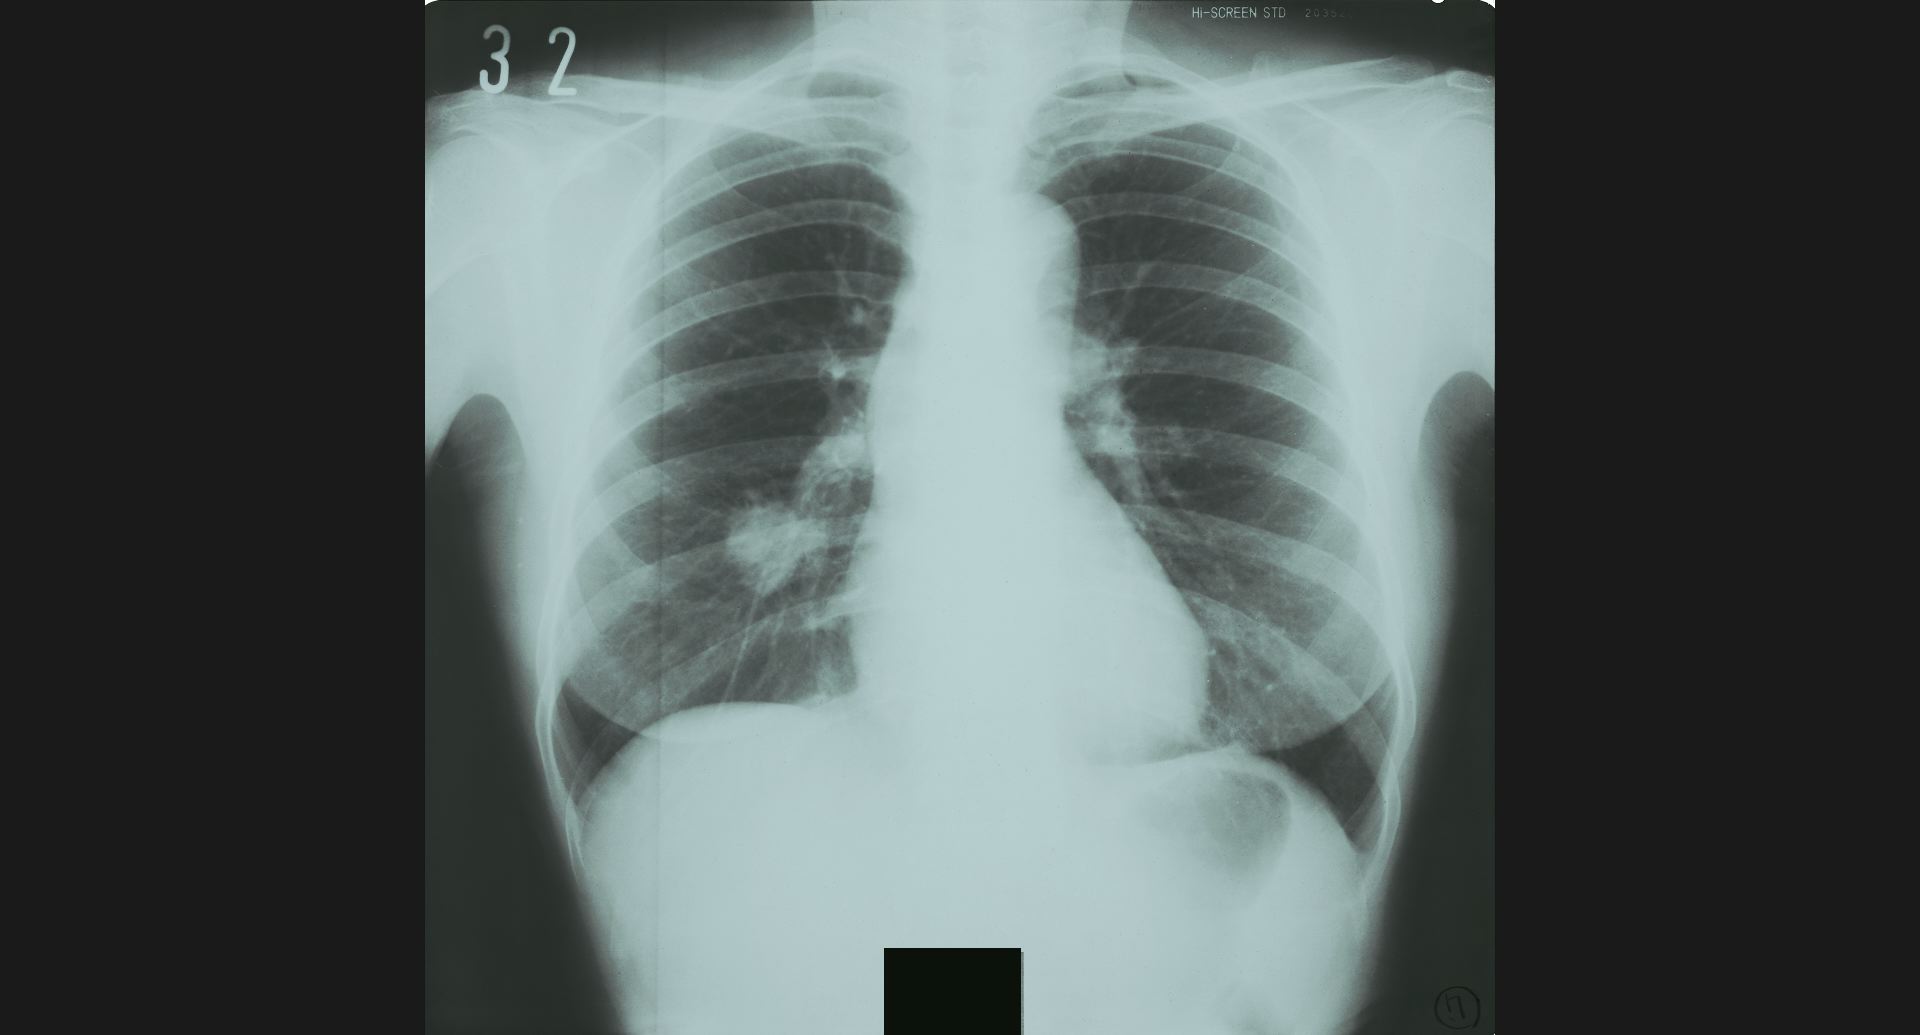

fig.8(87KB) :Lung abcess

cavity。